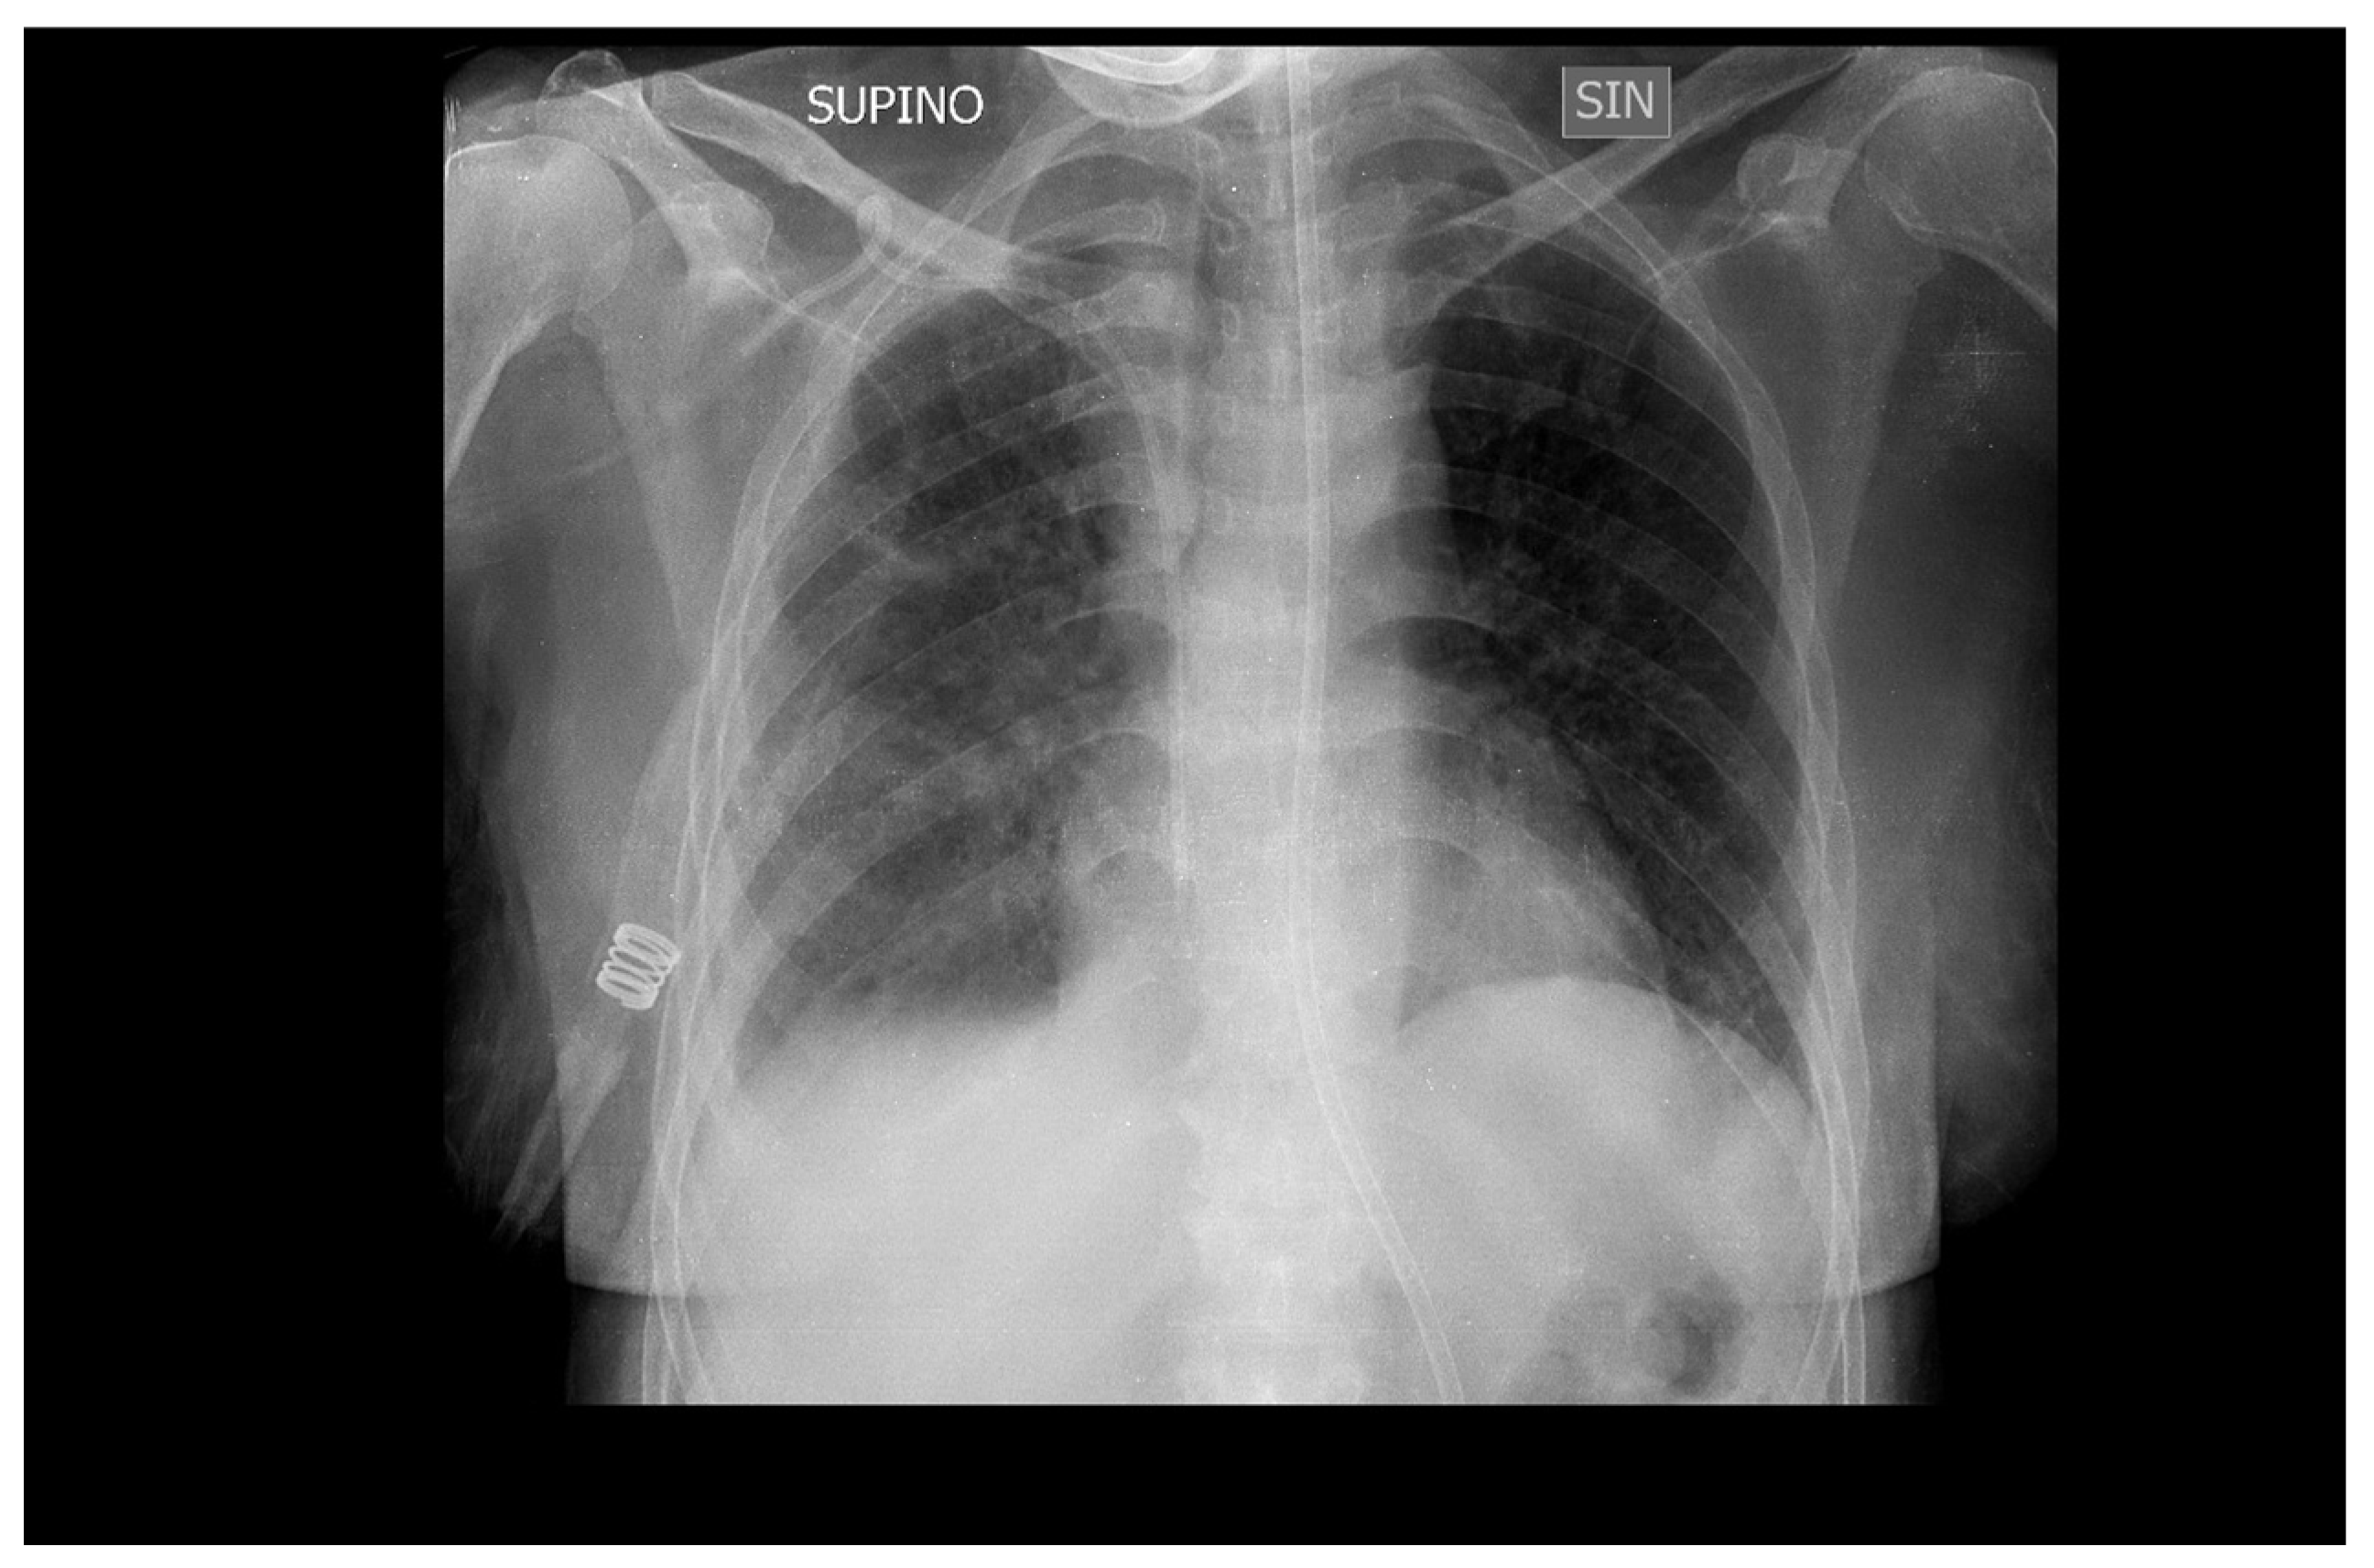

2. Case Presentation